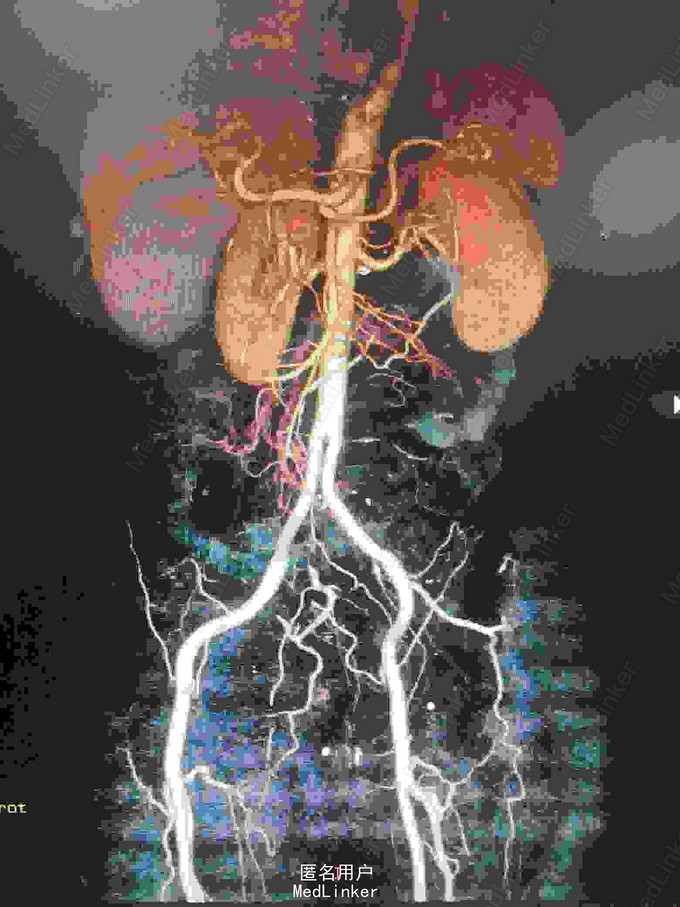

主诉:腰腹痛7月,加重一周。 病史:七月前发热后开始出现腰腹痛,呈持续性撕裂样痛,伴腹胀,症状反复。一周前腹痛症状加重。

体查:下腹部可触及搏动性包块。 辅助检查:腹部CT:腹主动脉假性动脉瘤并血栓形成,腰5椎体受侵蚀。血培养:沙门氏菌。

诊断:沙门氏菌感染性腹主动脉假性动脉瘤 处理:急诊行腹主动脉瘤切除人工血管置换术,术后予美罗培南抗感染8周,续以左氧氟沙星口服。

讨论:感染性腹主动脉假性动脉瘤较少见,致病菌以沙门氏菌最为常见。常见的手术方式为原位重建,旁路重建及支架植入,其中支架植入尚存较大争议。术后感染复发及死亡率仍较高,均需长时间抗感染治疗。